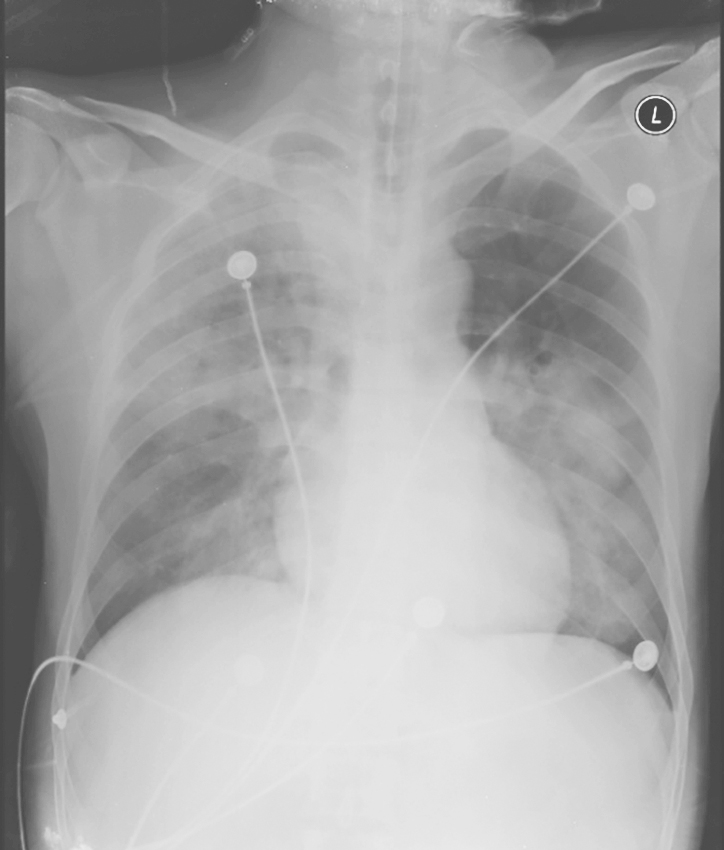

【影像学检查】

X线胸片(急诊):右肺及左肺中下野可见大片絮状模糊影(图1)。

图1 X线胸片表现